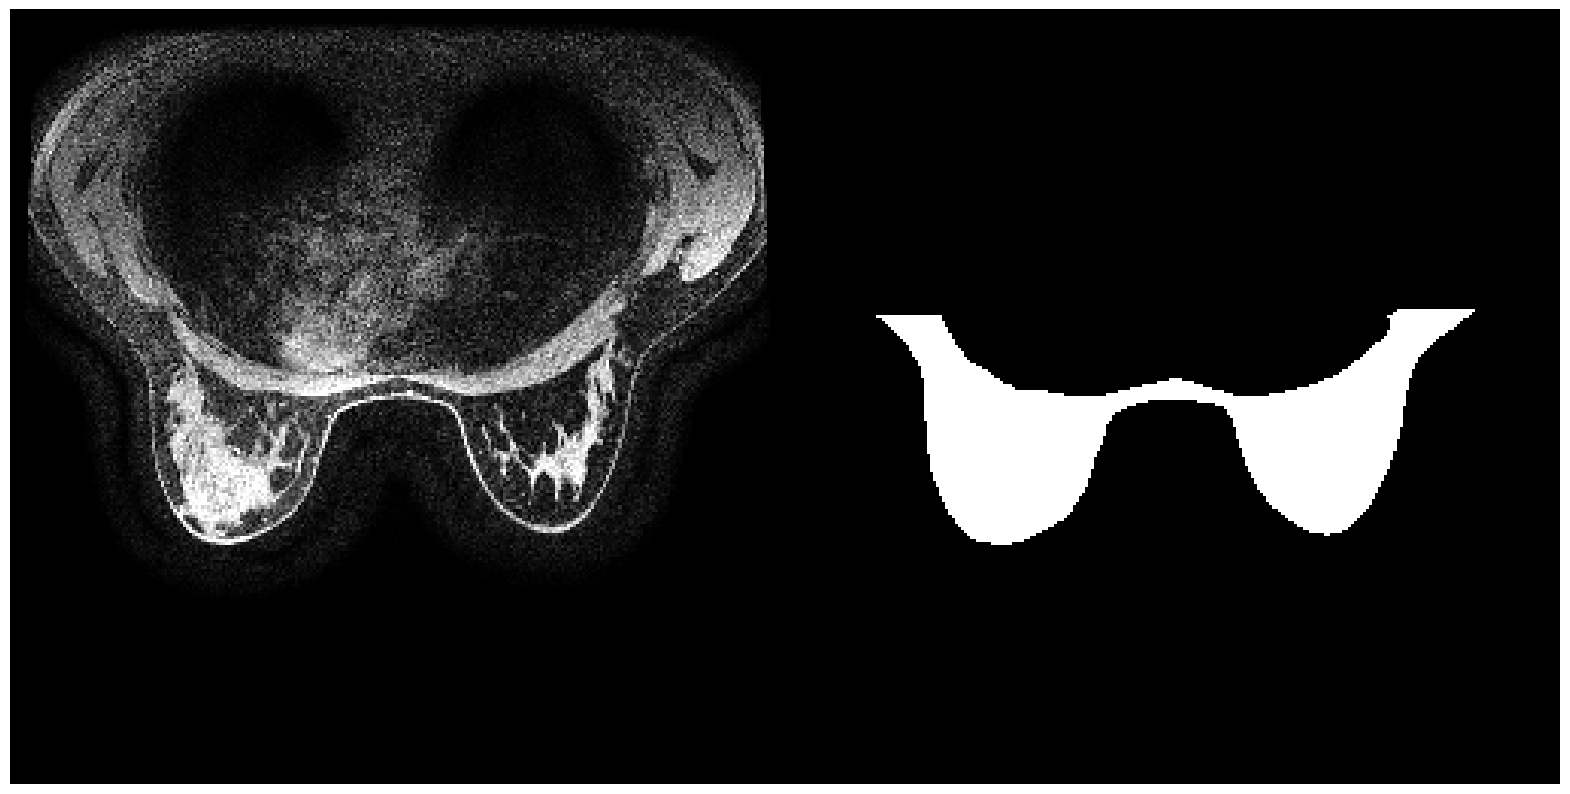

6.5.1 Validation with BFGT

The complete BFGT dataset contains 922 volumes of breast MRI images produced by GE and SIEMENS machines. We obtain 219 slices (up to 3 slices per volume) produced by the GE machine as our training and validation set. We then select 81 slices (up to 3 slices per volume) produced by SIEMENS as our out-of-domain dataset. Each image is resized to have the same dimension of 256×256256256256\times 256. We report below the mean IOUs and SBI of models trained on data with different augmentations.

Training set IOUvalsubscriptIOU𝑣𝑎𝑙\mbox{IOU}_{val} IOUnoisysubscriptIOU𝑛𝑜𝑖𝑠𝑦\mbox{IOU}_{noisy} IOUOODsubscriptIOU𝑂𝑂𝐷\mbox{IOU}_{OOD} SBI

No Augmentation 0.853 0.718 0.761 3.396

Color Jitter 0.830 0.744 0.820 3.726

NST 0.850 0.802 0.823 4.102

Sep. Color Jitter 0.872 0.730 0.780 3.696

Negative Insertion 0.867 0.717 0.748 3.996

Random Resized Crop 0.858 0.623 0.725 2.538

Random Crop Reflect 0.863 0.619 0.774 2.518

Table 4: Performance of models trained on datasets with different augmentations when applied to the validation set, dataset with noise injected, and dataset with naturally occurred domain shifts for BFGT

.

In experiments with BFGT, augmentations with no modifications on targets’ shapes achieved higher SBIs than the baseline model, while those that altered targets’ shapes resulted in models with smaller SBIs. This phenomenon matched our prediction. Color Jitter (brightness shifts for grayscale images), Sep. Color Jitter, and NST all lead to models with higher performance on OOD and Noisy data. In contrast, Negative Insertion showed no improvement in performance on OOD nor on Noisy data compared to the baseline, despite its higher SBI. This is because SBI also takes an SN’s performance on objects with dissimilar shapes into consideration. Random Resized Crop and Random Crop Reflect alter shape information in the training set. Both models have smaller SBIs than the baseline, plus similar or lower performance on OOD and noisy data. The results confirm that augmentation not altering shape improves models’ SBIs; Color Jitter and NST are apparently the most practical augmentation method to be applied to encourage shape learning and improve models’ generalizability.

Refer to caption

(a) Image from GE machine

(b) Image from SIEMENS machine

(c) The image collected from GE machine with (from left to right) Gaussian noise, shot noise, impulse noise, and defocus blur applied.

Figure 12: Samples from the three partitions of data domain in BFGT